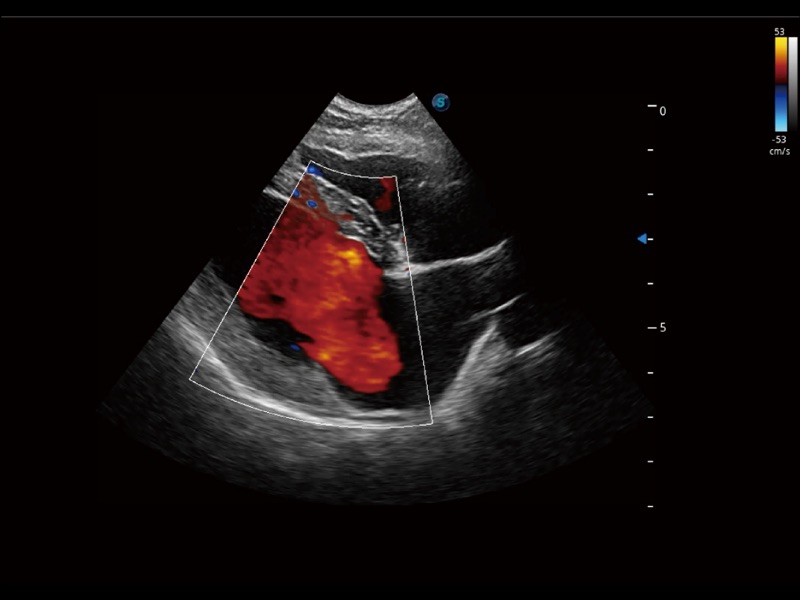

通過(guò)創(chuàng)新的 Matrix E自適應(yīng)濾波器和超長(zhǎng)時(shí)間域算法,極大提升超低速微細(xì)血流的檢出能力,同時(shí)更精準(zhǔn)地濾除軟組織和噪聲信號(hào),為獸用醫(yī)生提供以往無(wú)法通過(guò)常規(guī)血流獲得的疾病診斷信息。